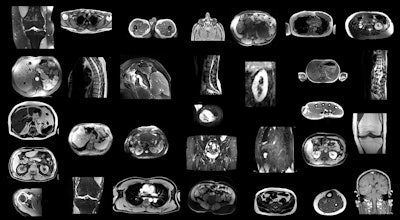

Example MRI scans in the training dataset. Since images were randomly sampled from clinical routine, the dataset contains a wide variety of different contrasts, pathologies, and image types. Images and caption courtesy of the RSNA.

To this end, D'Antonoli and colleagues built TotalSegmentator MRI, which they based on nnU-Net. They trained the model to produce sequence-independent segmentations of major anatomic structures using a dataset of 616 MR and 527 CT exams (total scans, 1,143). Of these, 1,088 (both CT and MRI exams) were used in a training set that included segmentations of 80 anatomic structures commonly used for measuring volume, characterizing disease, surgical planning, and opportunistic screening, while 55 (MRI exams only) were included in an internal test set. The team then assessed the model's performance using Dice scoring.